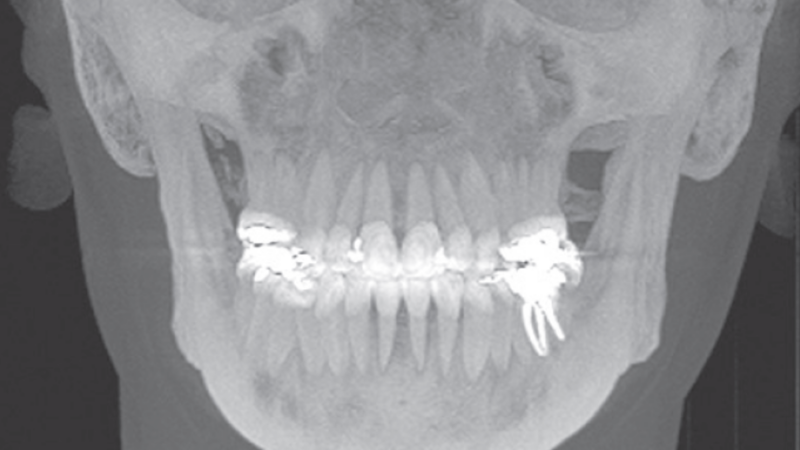

A tomografia computadorizada de feixe cônico faz aniversário! Entenda a mudança de paradigma na Odontologia.